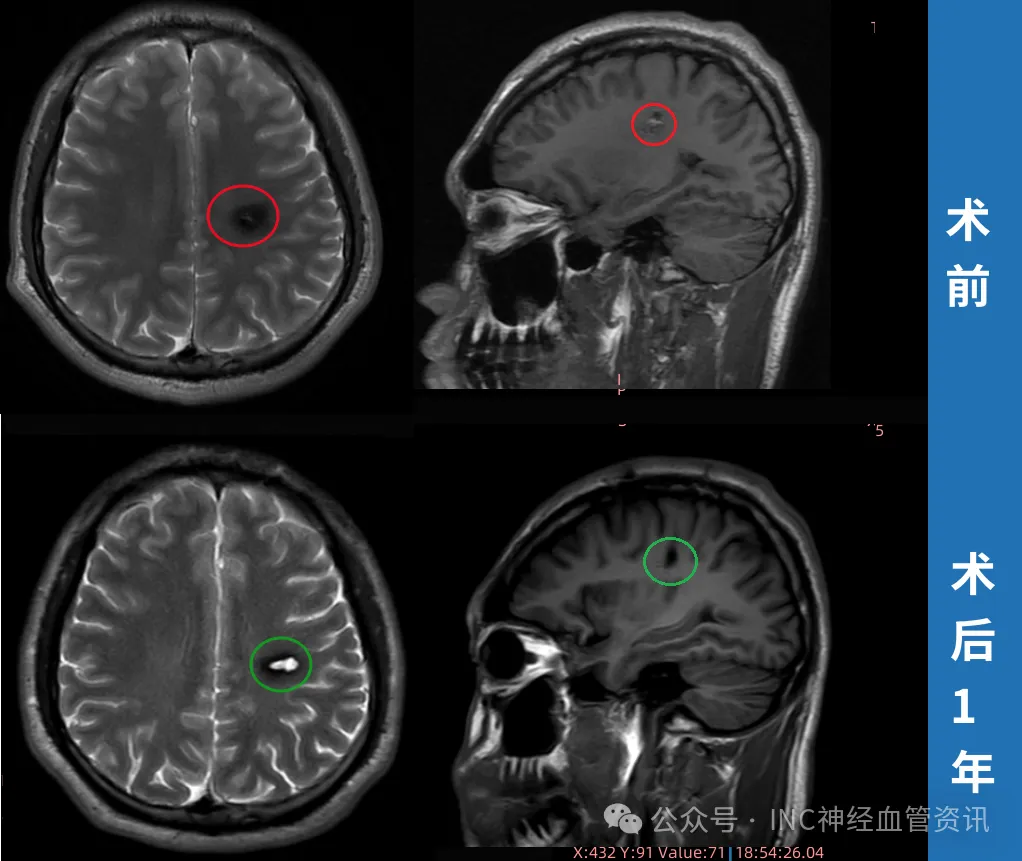

2023年3月手术前斌斌MRI影像

更棘手的是,斌斌的病灶体积小,精准定位难度更大——就像在麦田里找一颗特定的麦粒,既要挖出来,又不能碰倒周围的麦秆。

2023年4月9日,手术如期进行。术中导航实时定位病灶位置,巴教授凭借精湛的显微外科技术,在毫米级的空间里小心翼翼剥离病灶,最终将病灶完整取出。

术后4天,斌斌就能自己下床走动;术后2个月,他重新骑上了自行车;术后1年随访,MRI显示病灶无残留,周围脑组织干净.